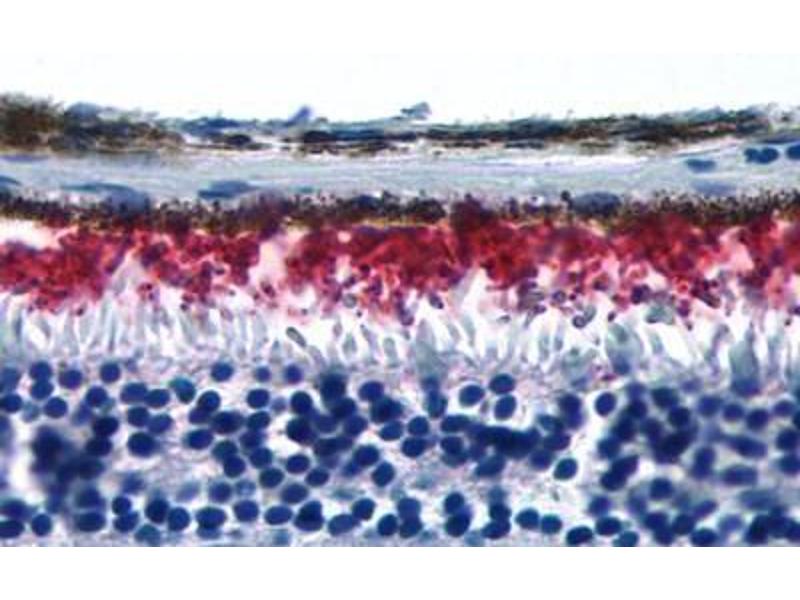

Rhodopsin Antikörper (Extracellular Domain)

Der Kaninchen Polyklonal anti-Rhodopsin Antikörper (ABIN1049292) detektiert spezifisch Rhodopsin in IHC und IHC (p). Dieser Antikörper reagiert spezifisch mit Proben aus Human, Ratte, Maus, Schwein, Affe und Kaninchen.

Immunohistochemistry (IHC), Immunohistochemistry (Paraffin-embedded Sections) (IHC (p))

Human RHO / Rhodopsin. BLAST analysis of the peptide immunogen showed no homology with other human proteins.

Synthetic 19 amino acid peptide from 2nd extracellular domain of human RHO / Rhodopsin. Percent identity with other species by BLAST analysis: Human, Monkey, Mouse, Rat, Rabbit, Pig, Cat, Elephant, Zebra finch (100%).

Approved: IHC, IHC-P (1 - 3 μg/mL)